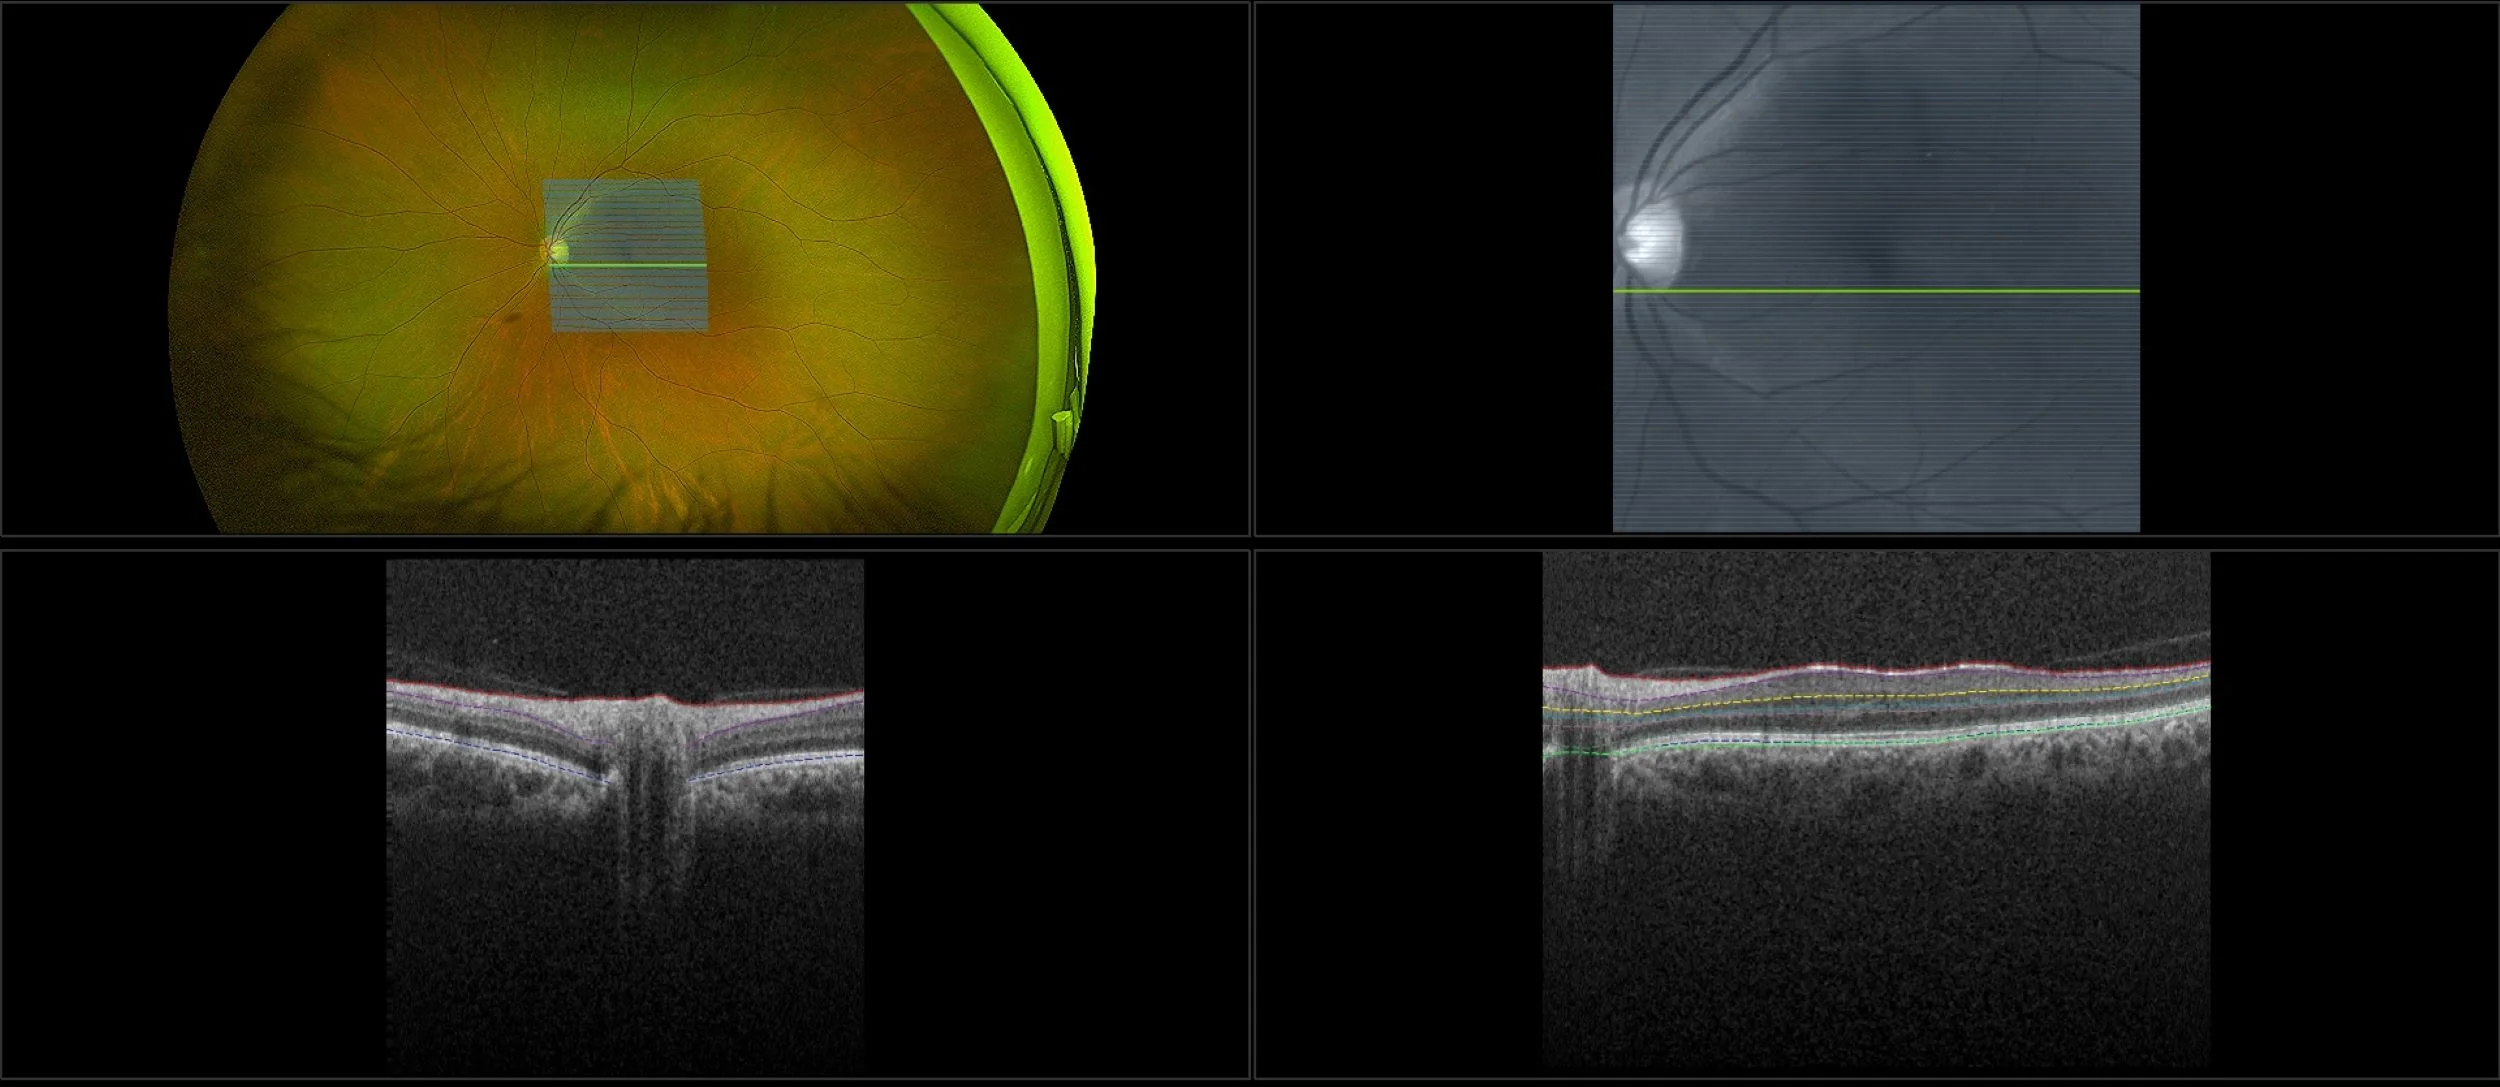

This material is designed as a searchable reference resource to support clinical decision-making. The information contained here should be used as general guidance when viewing optomap and OCT images from Optos devices. The differential diagnosis should be made under the direction of the responsible physician. These images were taken on the latest ultra-widefield optomap devices.

optomap Recognizing Pathology is searchable by pathology and/or optomap image modality. You may search by multiples of each selection. Each individual case is represented by the accompanying thumbnail image. Most cases include several different optomap image modalities. To view a full description of the case, please click on the thumbnail. Each image in the case will be made available through our OptosAdvance software which provides multi-dimensional visualization of digital images to aid in the analysis of anatomy and pathology. Support and pathology definitions can be found by selecting one of the buttons, above. Should you have questions, please complete the form below.